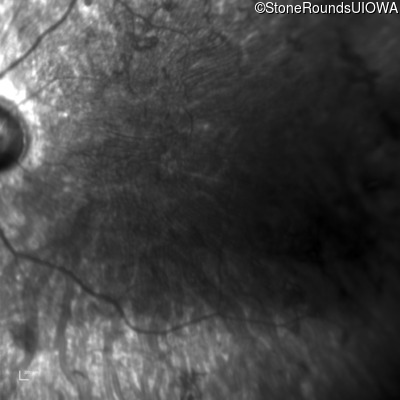

Infrared Fundus Photograph - Left - 5/140 sc

Exemplar